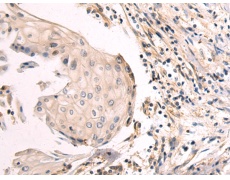

IHC positive control: |

Human esophagus cancer and Human colorectal cancer |

ELISA, IHC |